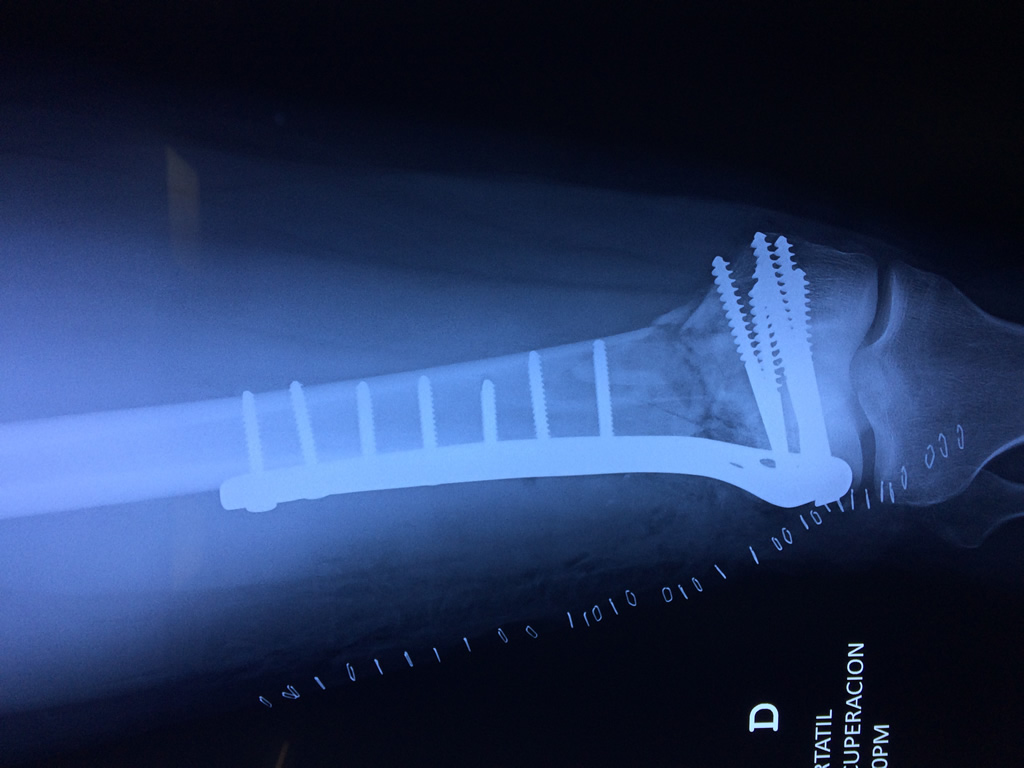

Fémur - Fémur

El fémur es el hueso del muslo, el segundo segmento del miembro inferior. Es el hueso más largo, fuerte y voluminoso del cuerpo humano.